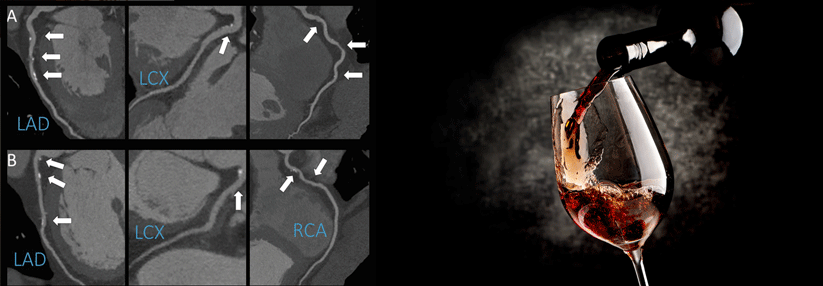

Bildgebende Verfahren zur Beurteilung der Koronararterien

• Koronarangiographie (Goldstandard)

• Mehrschicht-Spiral-CT, Dual-Source-CT

• MR-Angiographie

© Maria A Pantaleo, Anna Mandrioli, Maristella Saponara, Margherita Nannini, Giovanna Erente, Cristian Lolli and Guido Biasco : Development of coronary artery stenosis in a patient with metastatic renal cell carcinoma treated with sorafenib. BMC Cancer, 2012, 12:231 doi:10.1186/1471-2407-12-231, CC BY 2.0